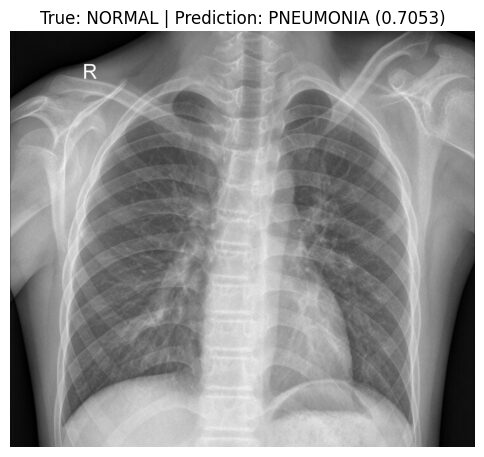

Predicting on random NORMAL image: IM-0011-0001-0001.jpeg

Actual class: NORMAL

Predicted class: PNEUMONIA

Confidence: 0.7053

Class probabilities: Normal=0.2947, Pneumonia=0.7053

Here, we took a random test X-ray image (IM-0011-0001-0001.jpeg) known to be NORMAL. Our model, however, incorrectly predicted it as PNEUMONIA with moderate confidence (approx. 70.5%).

This specific misclassification provides a clear example of the main weakness identified in our evaluation metrics: the model's difficulty in correctly recognizing NORMAL cases (achieving only ~38.0% recall/specificity according to the Classification Report). Errors like this, where NORMAL images are falsely predicted as PNEUMONIA (False Positives), are why the overall Precision for the PNEUMONIA class was limited to ~72.8%. ****When the model predicts PNEUMONIA, roughly 27% of those predictions are actually NORMAL cases being misclassified.

While the model remains excellent at catching actual PNEUMONIA (with ~99.5% recall/sensitivity), this tendency to misclassify NORMAL images highlights the impact of the class imbalance. Looking at the specific image, we can see prominent normal structures (bronchial/vascular markings); it's plausible that the model, biased by the imbalance, struggles to differentiate these complex normal patterns from potential abnormalities.